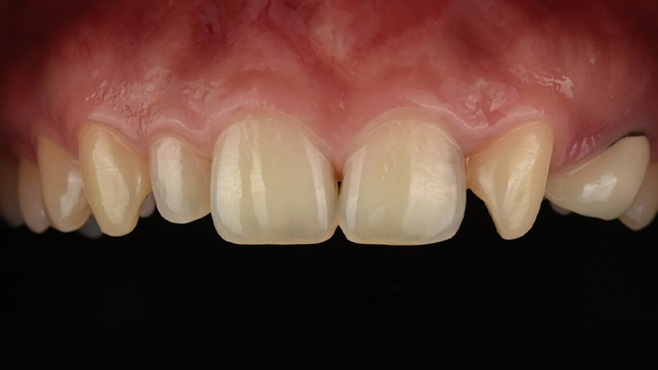

맞는 건 괜찮은데… 충치는 못 참겠습니다|20대 격투기 선수 치과 방문기

2026.02.06